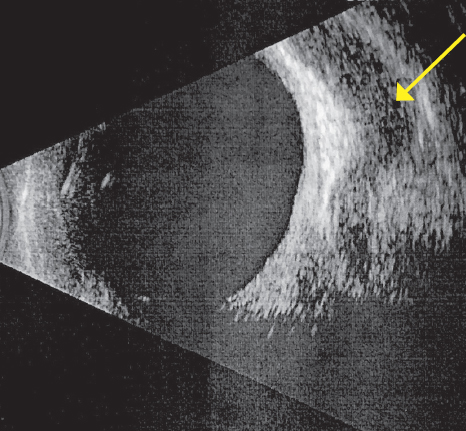

Ультразвуковое исследование орбит: визуализируется расширенная верхняя глазная вена OD (рис. 3).

Рис. 3. Расширенная верхняя глазная вена правой орбиты (стрелка)

Fig. 3. Dilated superior ophthalmic vein of the right orbit (arrow)